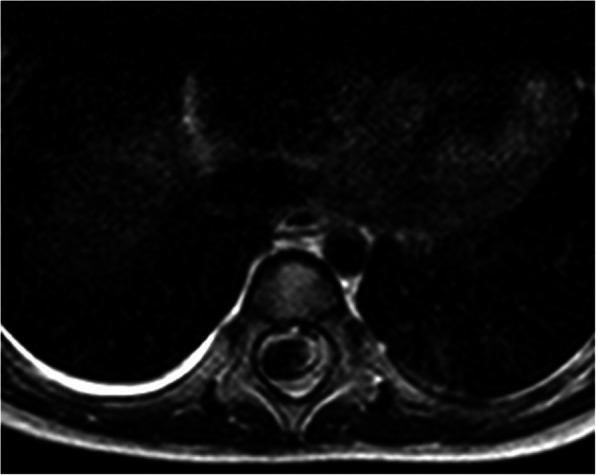

The emergent angiogram was performed under general anesthesia. Patient received combined intravenous and inhalation induction with propofol and sevoflurane. Two large bore IVs were established in anticipation of blood loss. The patient was found to have a complex type IVc AVM (Fig. 2) and fistula from the Artery of Adamkiewicz at L1-L2. She also had perimedullary dilated veins and a pseudoaneurysm that measured 2.5 cm × 1.5 cm × 1.5 cm. The pseudoaneurysm compressed the spinal cord at T8-T10 (Fig. 3), displacing it from right to left.

Fig. 3.

Axial T2 weighted image at T10 level showing the flow void of the AVM pseudoaneurysm occupying nearly the entire spinal canal and compressing the spinal cord from right to left